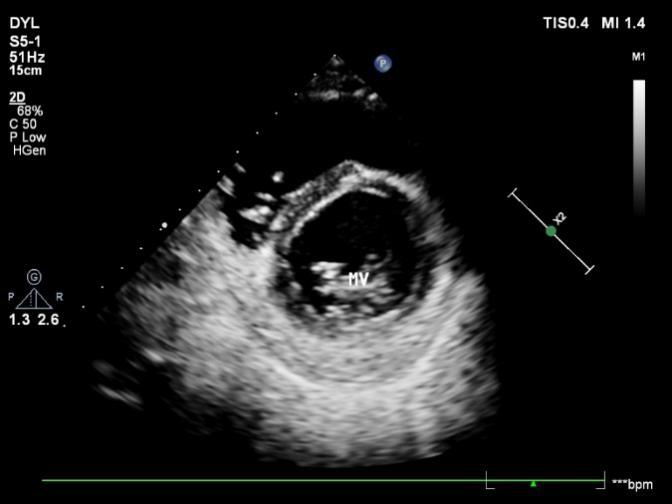

1.2.2二尖瓣水平

胸骨旁左室短轴切面二尖瓣水平二维超声胸骨旁左室短轴切面二尖瓣水平二维超声